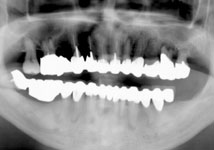

歯周病が進行し、両奥歯が噛みにくく見た目も悪いということで受診されました。

歯周再生治療と審美補綴治療によってトータルコーディネートしました。

今ではしっかり噛めるようになり、見た目も良くなったと満足されています。 |